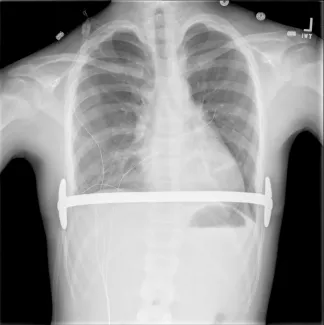

Repair with a metal pectus bar, called the Nuss Procedure, is achieved by bending a stainless bar to fit the chest wall. The bar is then inserted and secured through a small incision under each arm using the aid of a endoscope to monitor and avoid injury to the heart during insertion. The bar goes over the ribs and under the sternum, to push the sternum forward into the new position. The ends of the bar are secured to the chest wall. This procedure takes between 1–2 hours.

Preoperatively, your insurance carrier may require a CT scan to measure the Pectus Severity Index (PSI, also known as the Haller Index), which is the the ratio of the width of the chest wall to the depth at the deepest point of the deformity. This value usually must exceed 3.2 to be considered severe enough to be surgically corrected.

- Sports may be resumed as soon as the surgeon determines this is safe. Some contact sports may be not be permitted while the bar is in place. The bar may prevent adequate chest compressions during CPR and defibrillation requires paddle adjustment to be effective.

- No MRI should be done while the Pectus bar in in place.

- Use of a medical alert bracelet or necklace is recommended at all times in order to notify emergency providers of the presence of a Pectus bar. Recommended bracelet text: Steel bar in chest. CPR more force. Cardioversion ant/post paddle placement.